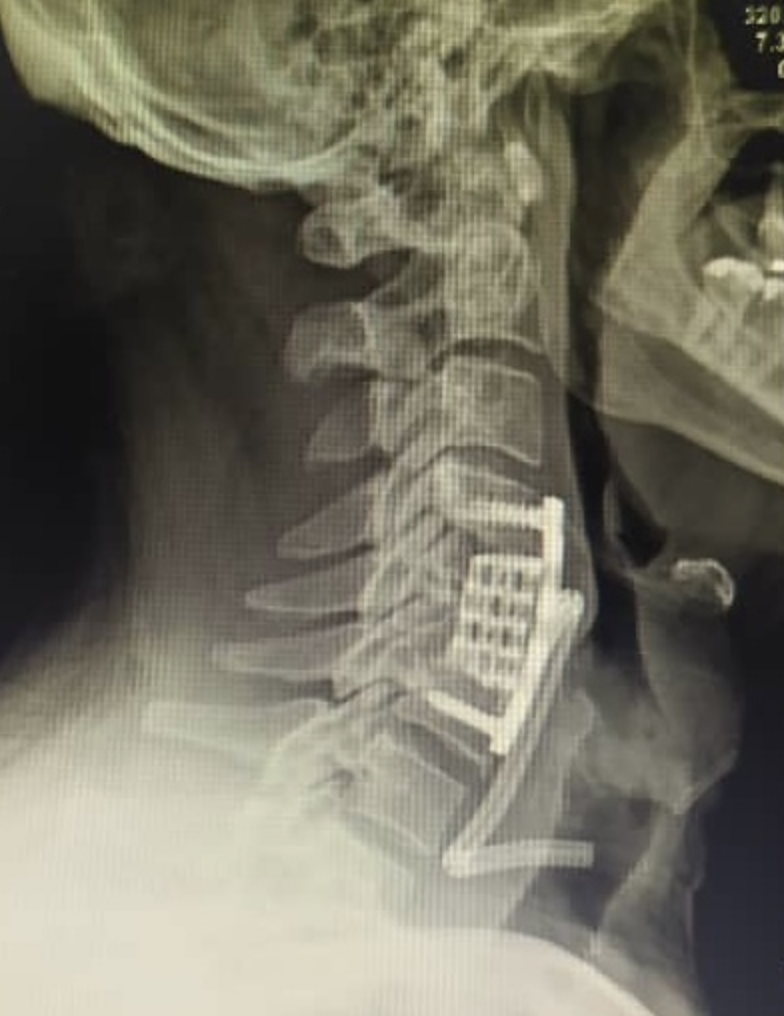

Esta es la placa post-operatoria inmediata donde se colocó una cesta en el sitio donde se quitó la vértebra y se reforzó con una placa por vía anterior. Se pudo realizar una descompresión completa de la médula.